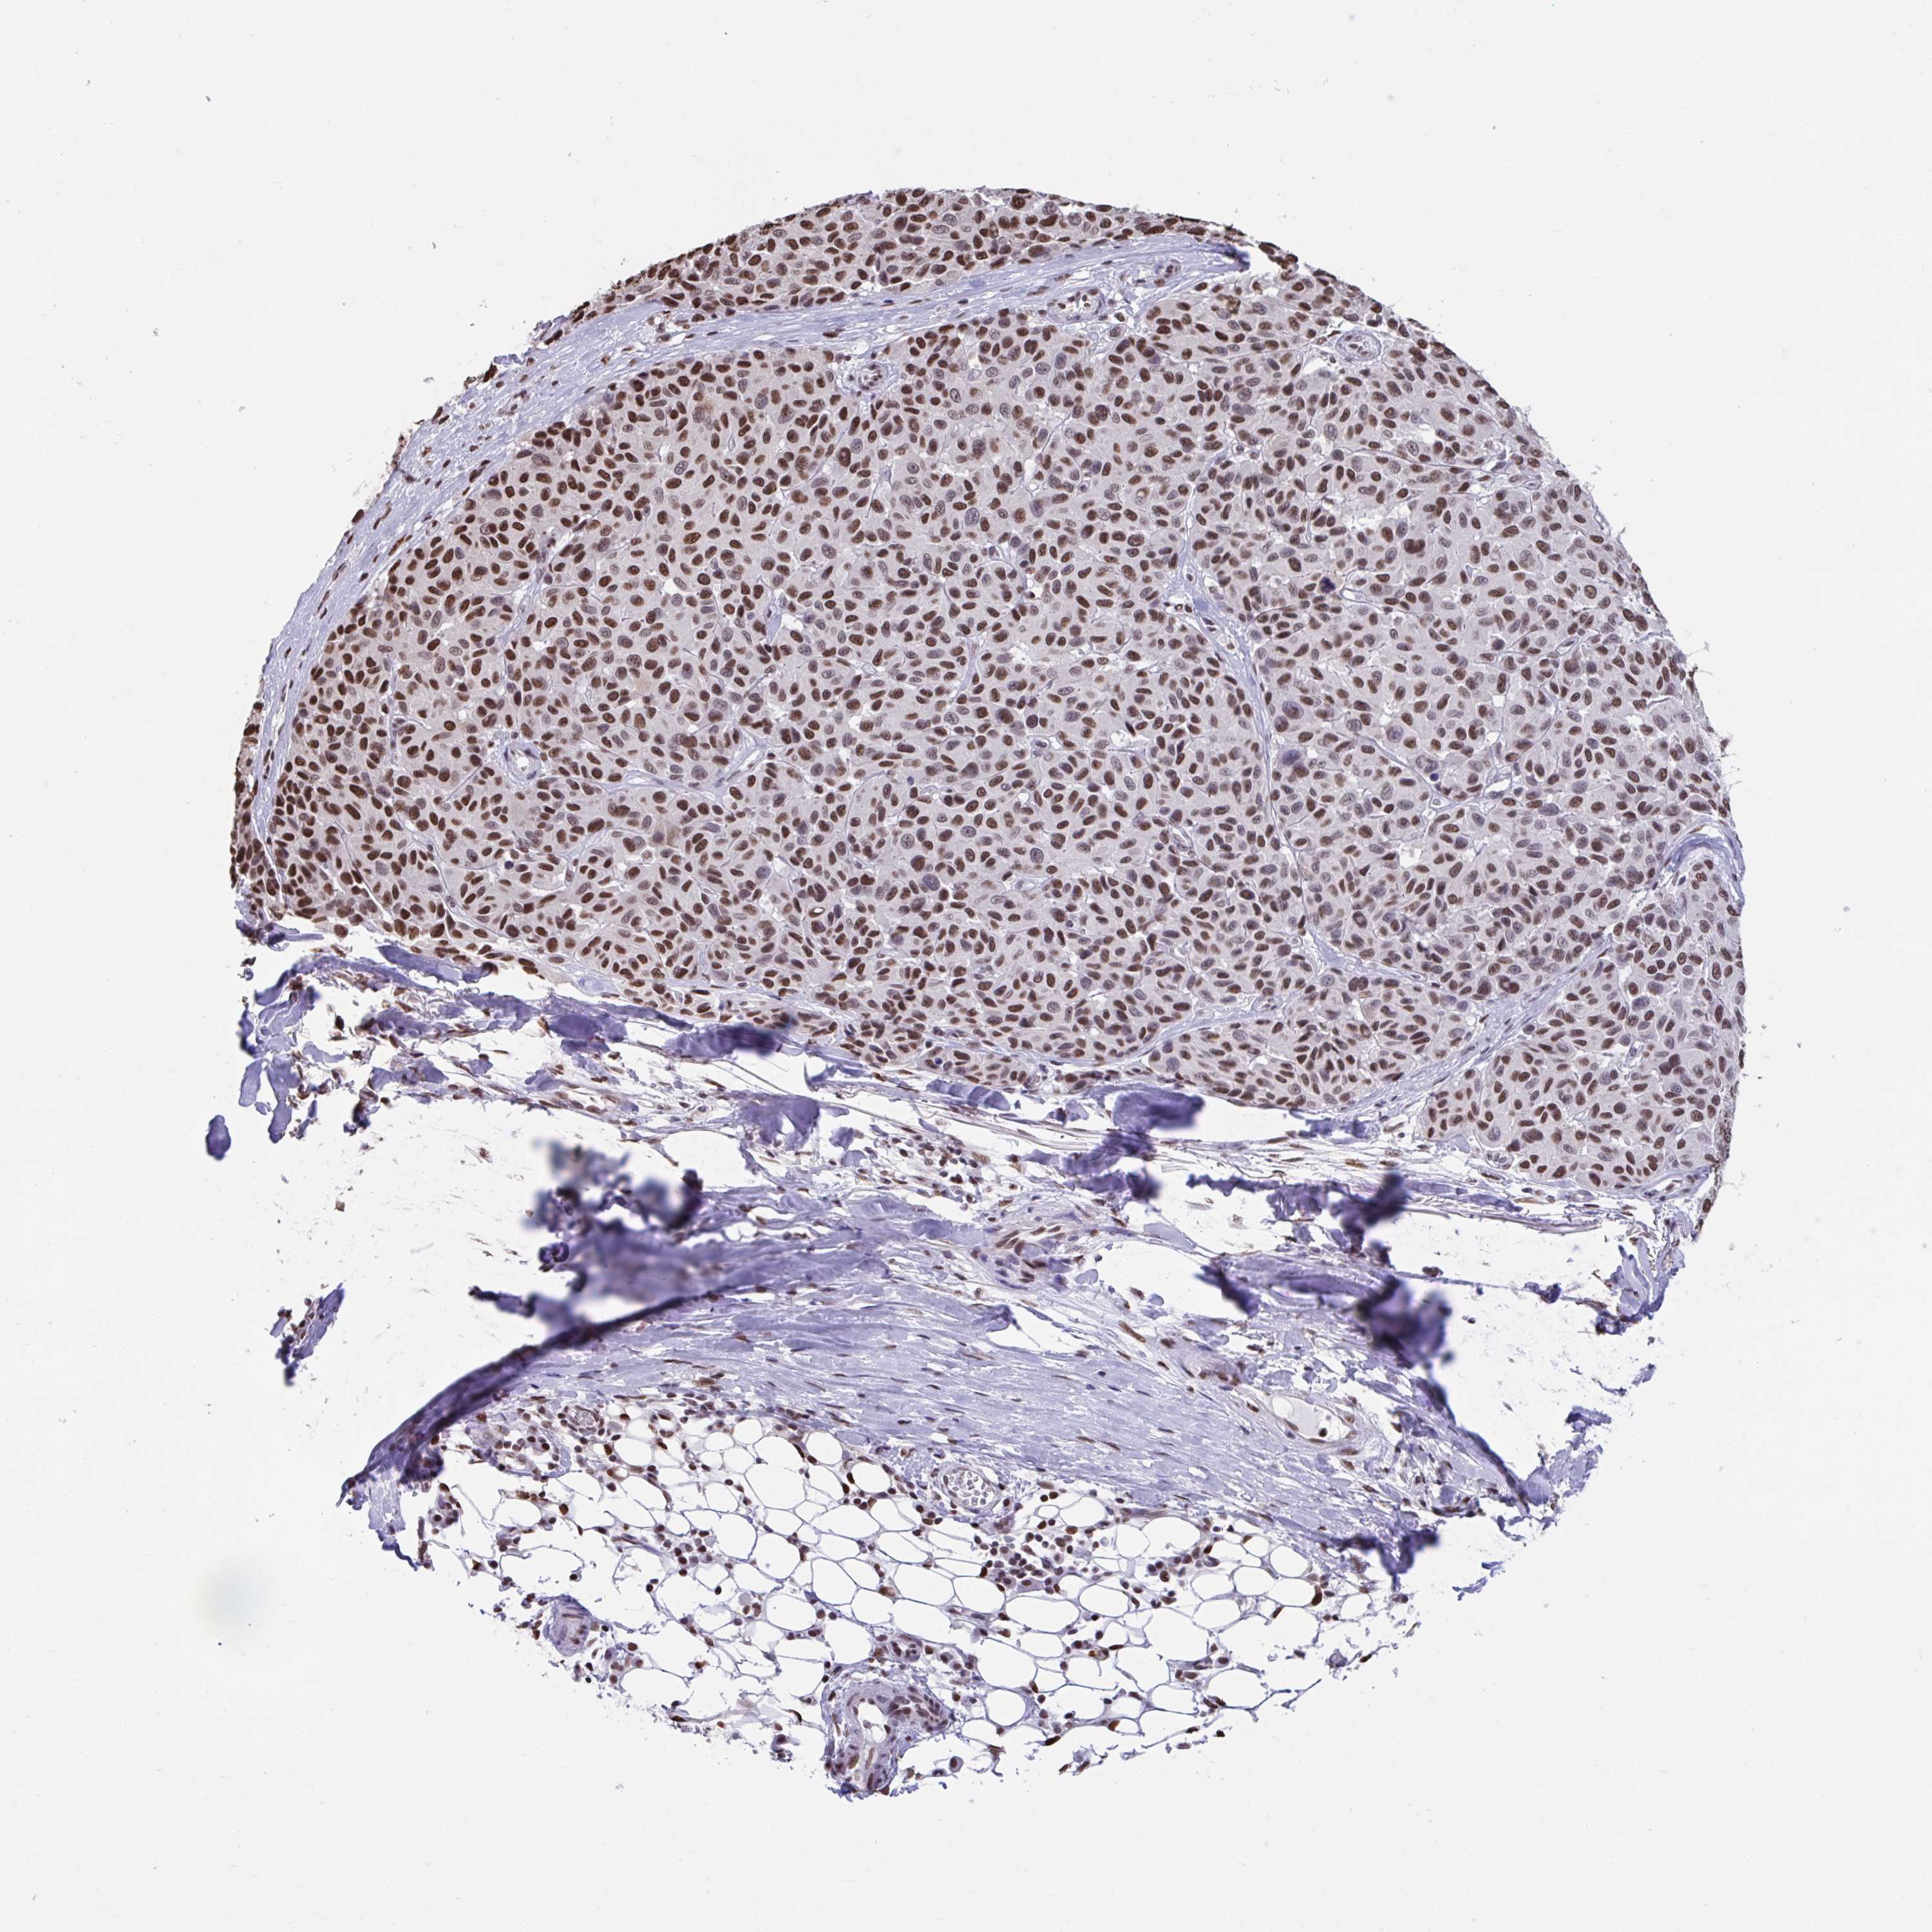

MELANOMA - Protein expressioni

A mouse-over function shows sample information and annotation data. Click on an image to view it in a full screen mode. Samples can be filtered based on level of antibody staining by selecting one or several of the following categories: high, medium, low and not detected. The assay and annotation is described here.

Note that samples used for immunohistochemistry by the Human Protein Atlas do not correspond to samples in the TCGA dataset.

Antibody stainingi

Antibody staining in the annotated cell types in the current human tissue is reported as not detected, low, medium, or high, based on conventional immunohistochemistry profiling in selected tissues. This score is based on the combination of the staining intensity and fraction of stained cells.

Each image is clickable and will lead to virtual microscopy that enables deeper exploration of all samples and also displays staining intensity scores, fraction scores and subcellular localization as well as patient and tissue information for each sample.

Antibody HPA056820

Antibody HPA063147

Staining

High

Medium

Low

Not detected

Intensity

Strong

Moderate

Weak

Negative

Quantity

>75%

75%-25%

<25%

None

Location

Nuclear

Cytoplasmic/membranous

Cytoplasmic/membranous,nuclear

Malignant melanoma, Metastatic site

Malignant melanoma, NOS